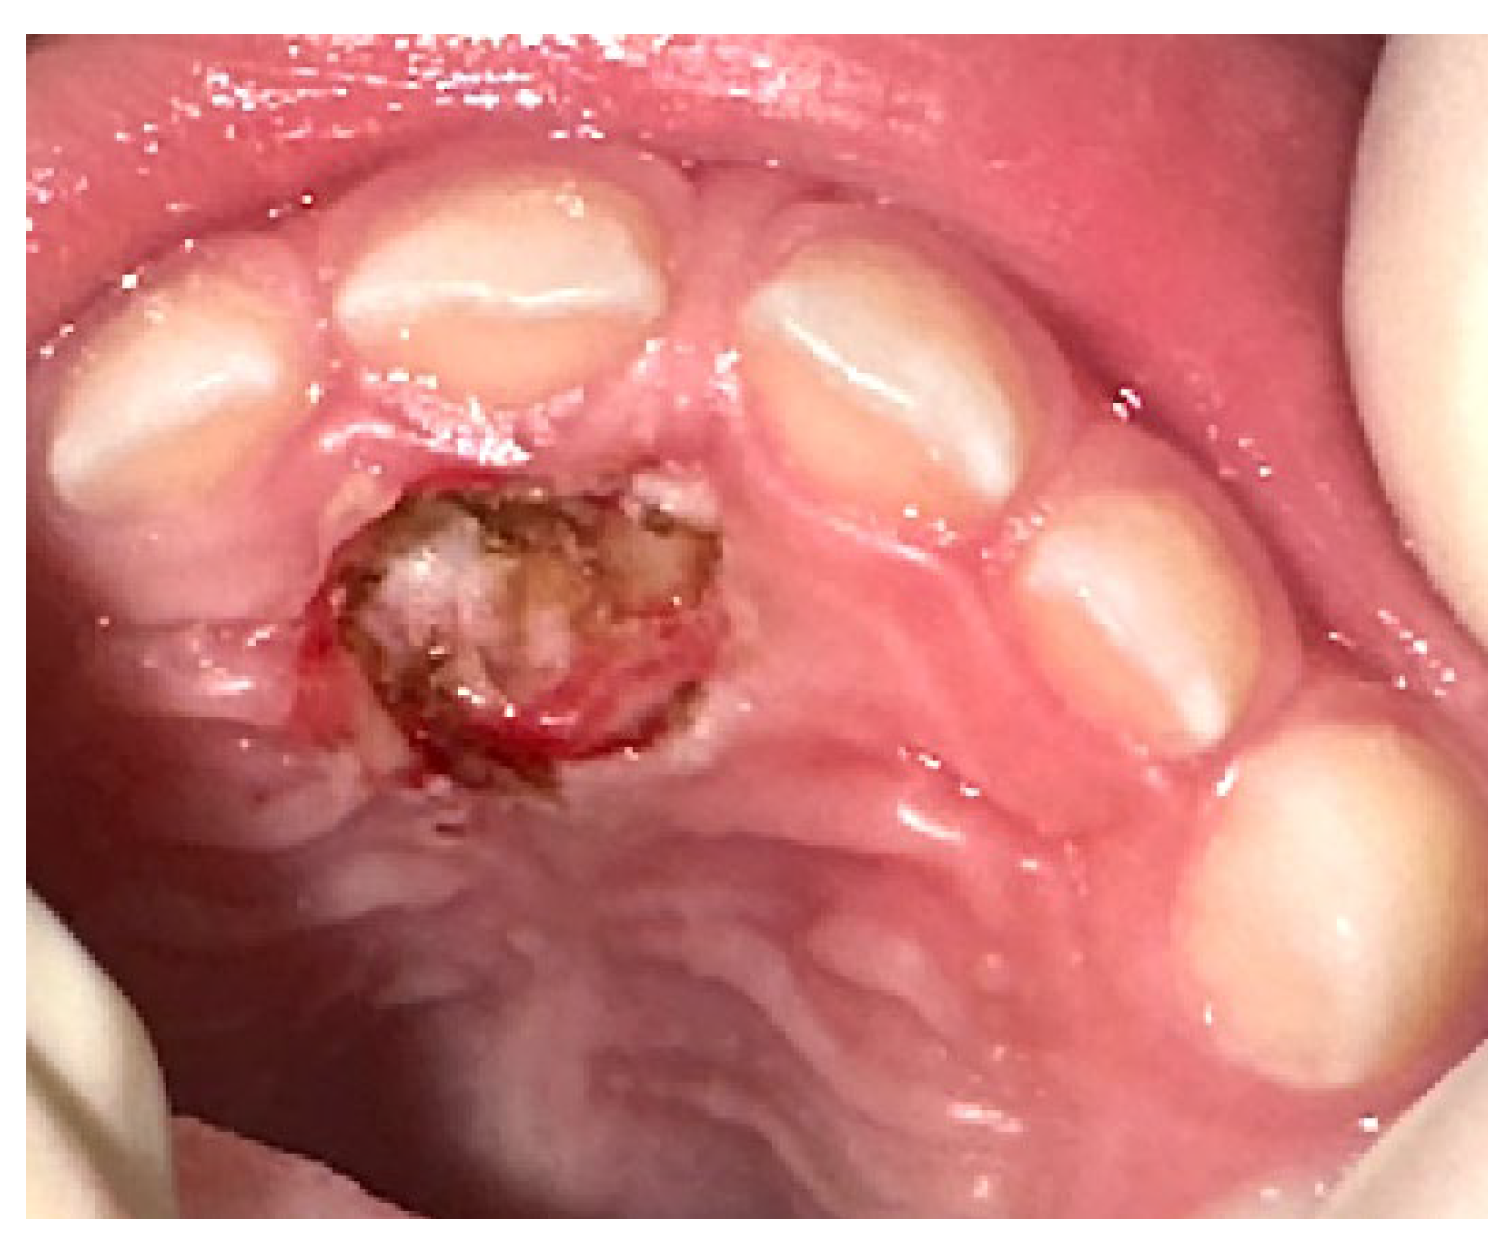

2015 | 1 | 11 | F | Anterior maxilla Right canine region |

4 × 3 cm | sessile exophytic lesion without changes in color, indurations, or ulceration. | OPT CT |

General anesthesia | POF | No |